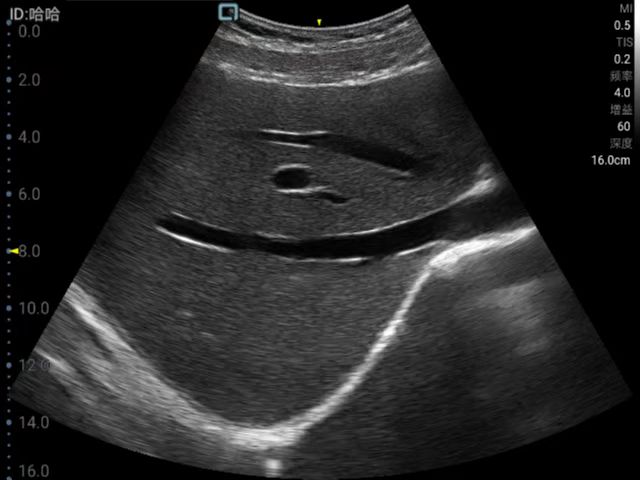

General practice use (mainly divided into ultrasound diagnostic systems for cardiovascular, abdominal, superficial organs, fetus, abdominal large blood vessels and limb blood vessels. Superficial organs mainly include diseases of thyroid, breast, eye, testis, scrotum, etc. Generally, high-frequency probes are used. Abdominal organs are mainly divided into digestive system, urinary system, gynecology, including uterus, accessories and other diseases. Fetal diagnosis in normal fetuses in the early, middle and late stages, mainly observe fetal growth and development, examination of Amniotic fluid, umbilical cord, placenta. Vascular ultrasound diagnosis, including carotid artery, abdominal large blood vessels and blood vessels of limbs, to know whether there is plaque and stenosis in arteries, and whether there is thrombus in veins; for the heart, mainly detect whether there are abnormalities in intracardiac structure and hemodynamic changes.), remote diagnosis.